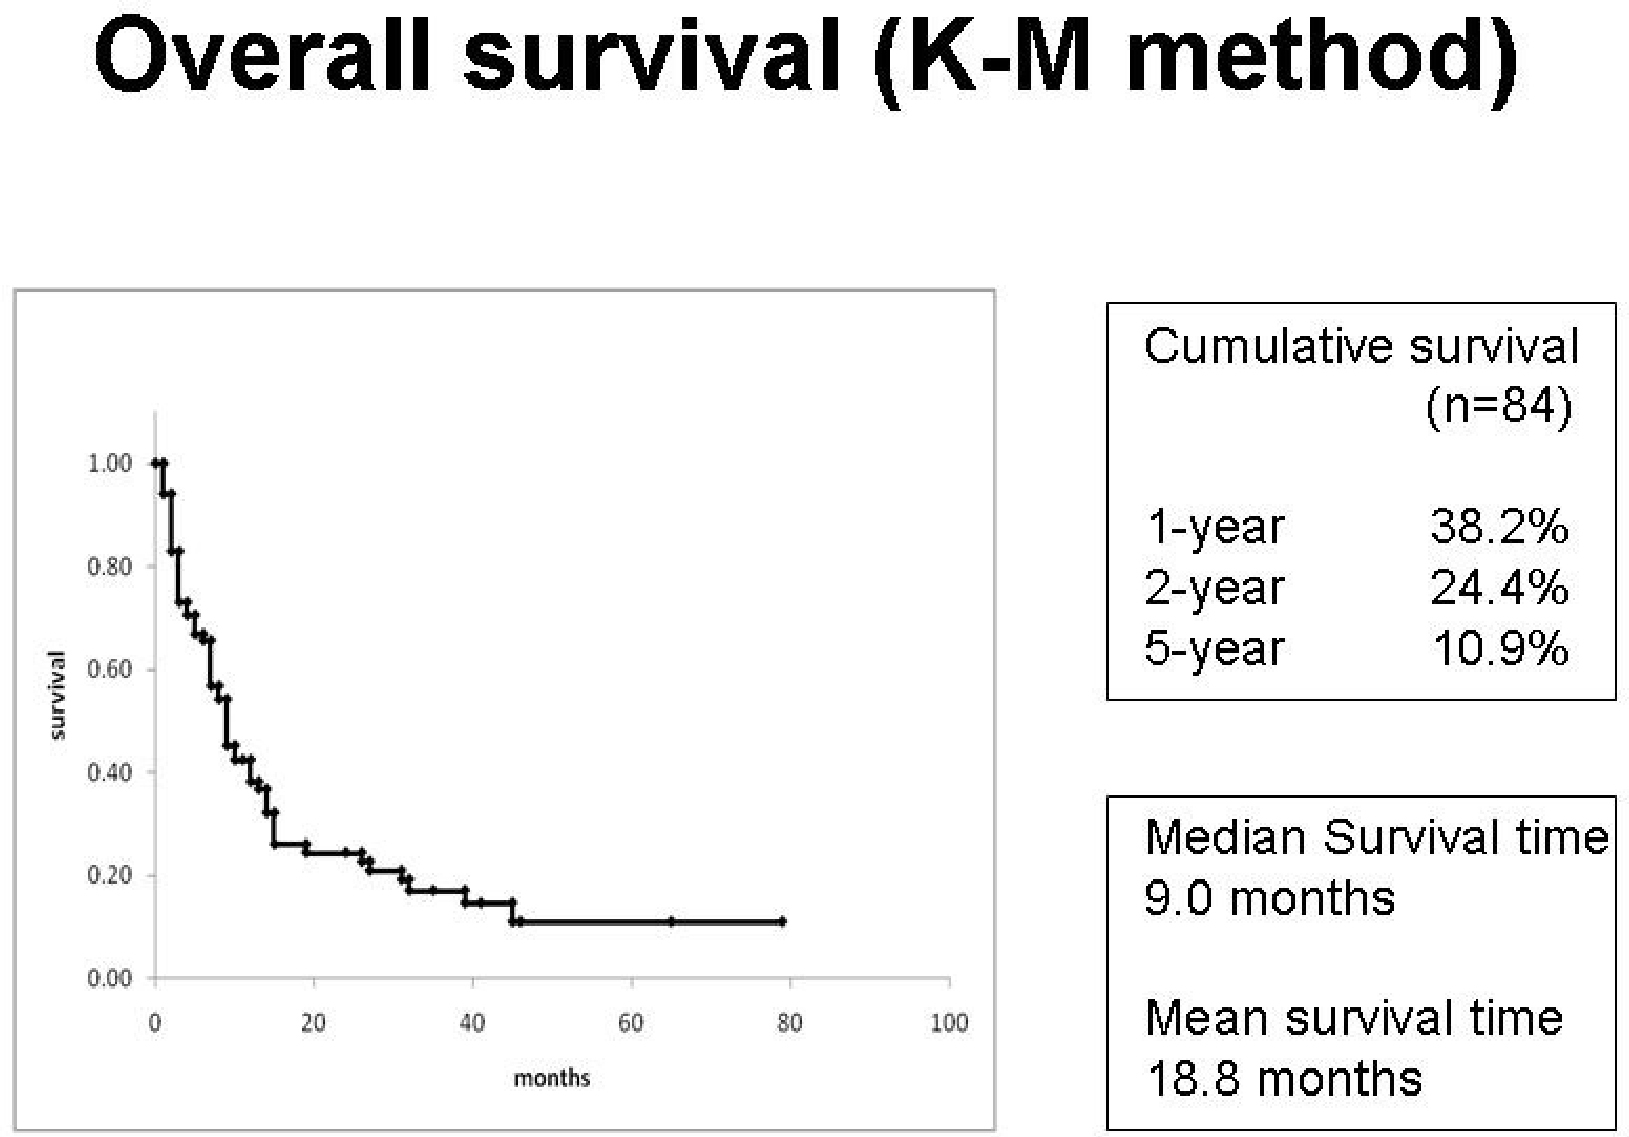

脳転移 転移性脳腫瘍 でもあきらめない 10年生存例の解析 がん

脳転移 転移性脳腫瘍 でもあきらめない 10年生存例の解析 がん

乳がんが脳転移した時の生存率 症状 治療法について解説する がん

乳がんが脳転移した時の生存率 症状 治療法について解説する がん